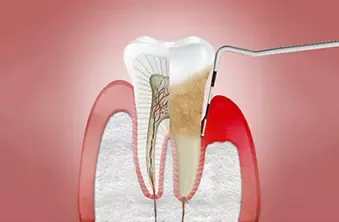

Z vsemi naštetimi postopki poskrbimo za zmanjšanje krvavenja dlesni in preprečujemo razvoj parodontoze.

Peskanje se izvaja s posebnim prahom pod pritiskom. Je varno in neboleče. Izvaja ga ustni higienik ali zobozdravnik. Po peskanju sledi poliranje zob, s čimer zgladimo zobne površine.